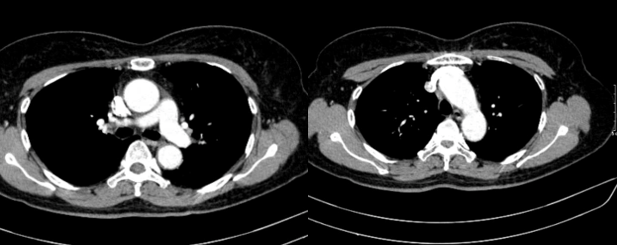

– Chụp cắt lớp vi tính lồng ngực: Nhu mô thùy trên phổi (Phải) có nốt tổn thương kích thước 13x14mm, bờ không đều, ngấm thuốc, sau tiêm. Rải rác nốt đặc 2 bên thùy phổi kích thước 3-10mm. Trung thất các nhóm 1R; 2R; 4R; 5; 8; 10RL có vài hạch lớn nhất kích thước 26x15mm; bờ không đều; ngấm thuốc không đồng nhất sau tiêm. Thượng đòn 2 bên có vài hạch tính chất tương tự; hạch bên phải kích thước 11x14mm

Hình 1. Hình ảnh cắt lớp vi tính ngực có tiêm: thùy trên phổi (P) có nốt tổn thương kích thước 13x14mm, bờ không đều, ngấm thuốc, sau tiêm. Nghi ngờ tổn thương nguyên phát (mũi tên đỏ)

Hình 2: Hình ảnh cắt lớp vi tính ngực có tiêm: Rải rác nốt đặc 2 bên thùy phổi kích thước 3-10mm (các mũi tên màu xanh lá)

Hình 3: Hình ảnh cắt lớp vi tính ngực có tiêm: Trung thất các nhóm 1R; 2R; 4R; 5; 8; 10RL có vài hạch lớn nhất kích thước 26x15mm; bờ không đều; ngấm thuốc không đồng nhất sau tiêm (mũi tên màu cam)